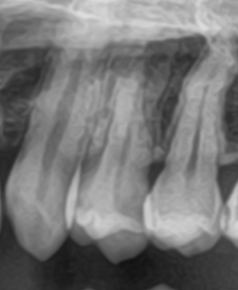

例をあげますと、下の写真は通常の縦横のレントゲンですが、真ん中の歯が虫歯なのですが不鮮明でどのくらいの大きさかよくわかりません。

下の写真はCTですが、CTでみると縦横奥行き虫歯が鮮明に確認できます。一部の所では非常に神経に近い所まで虫歯が大きくなっているのがわかりました。

事前にこのような状況がわかるので、この歯は神経を抜くことなく、無事に1回で治療を終える事が出来ました。

このように2次元のレントゲンだけでは、「小さい虫歯と思って治療を始めてみたら、実は大きかった」ということになるのが多いです。前述の通り一般的な歯科医院の虫歯治療は非常に短い時間で終わらないといけないので、心理的に焦ってしまいます。それが、削りすぎて神経を痛めて抜くことになってしまったり、つめ物がすき間や段差の多いものになってしまったりするのです。